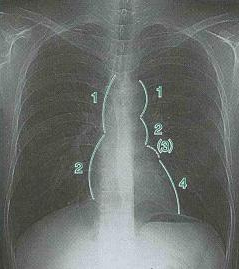

胸部レントゲンでは心臓の陰影は右を2弓、左4弓に分けられる。それぞれ対応する解剖学的構造は以下のとおり

右1弓:上大静脈

右2弓:右房

左1弓:大動脈弓

左2弓:肺動脈

左3弓:左房

左4弓:左室